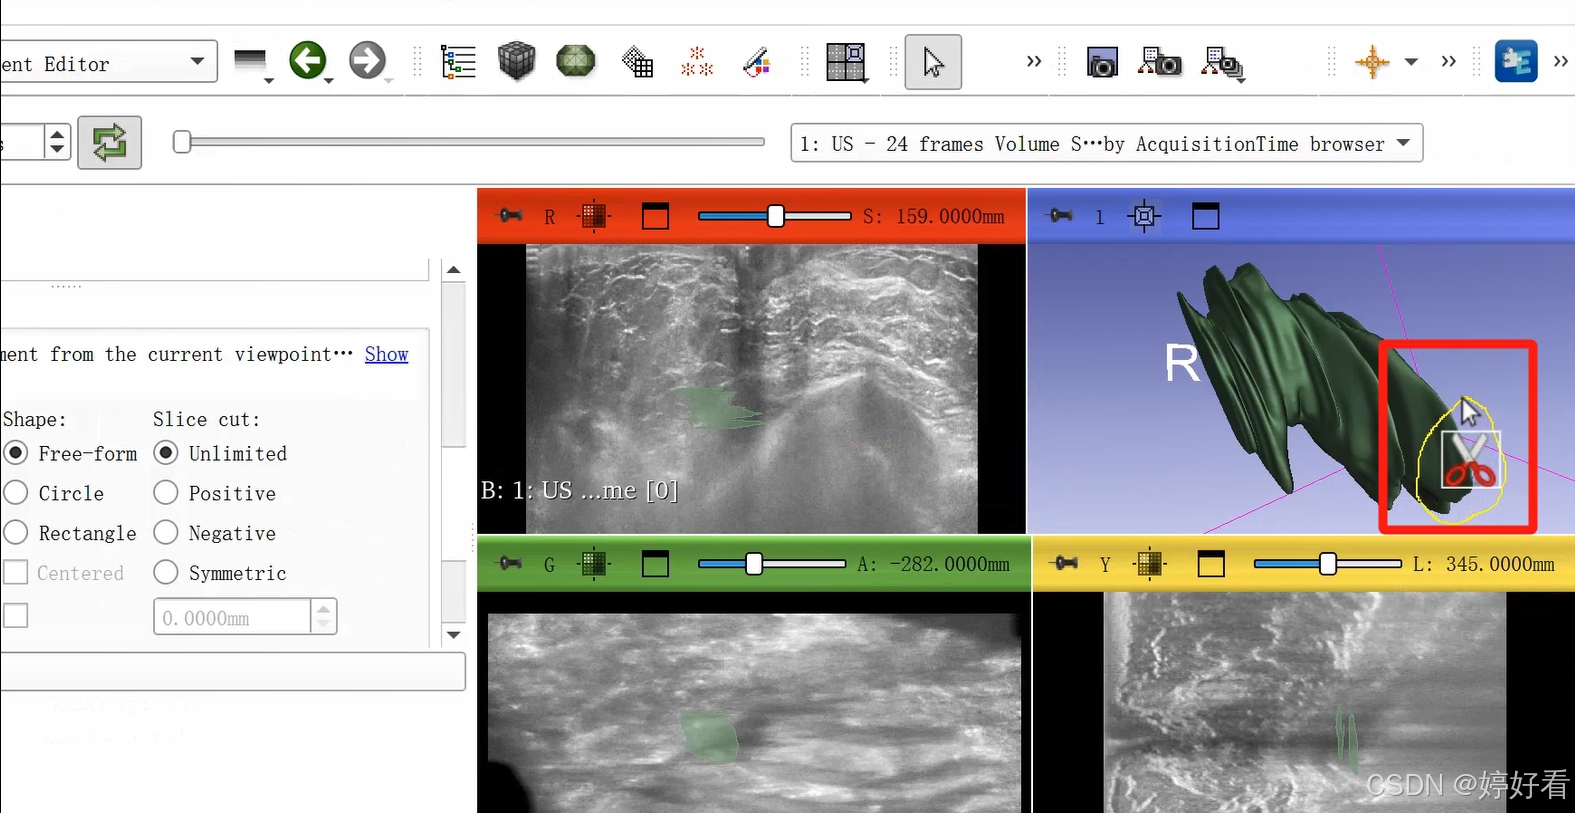

2.8 剪刀功能

剪刀功能的选项较多。以第一个Erase inside功能为例,也就是把圈起来部分里面的内容减掉。